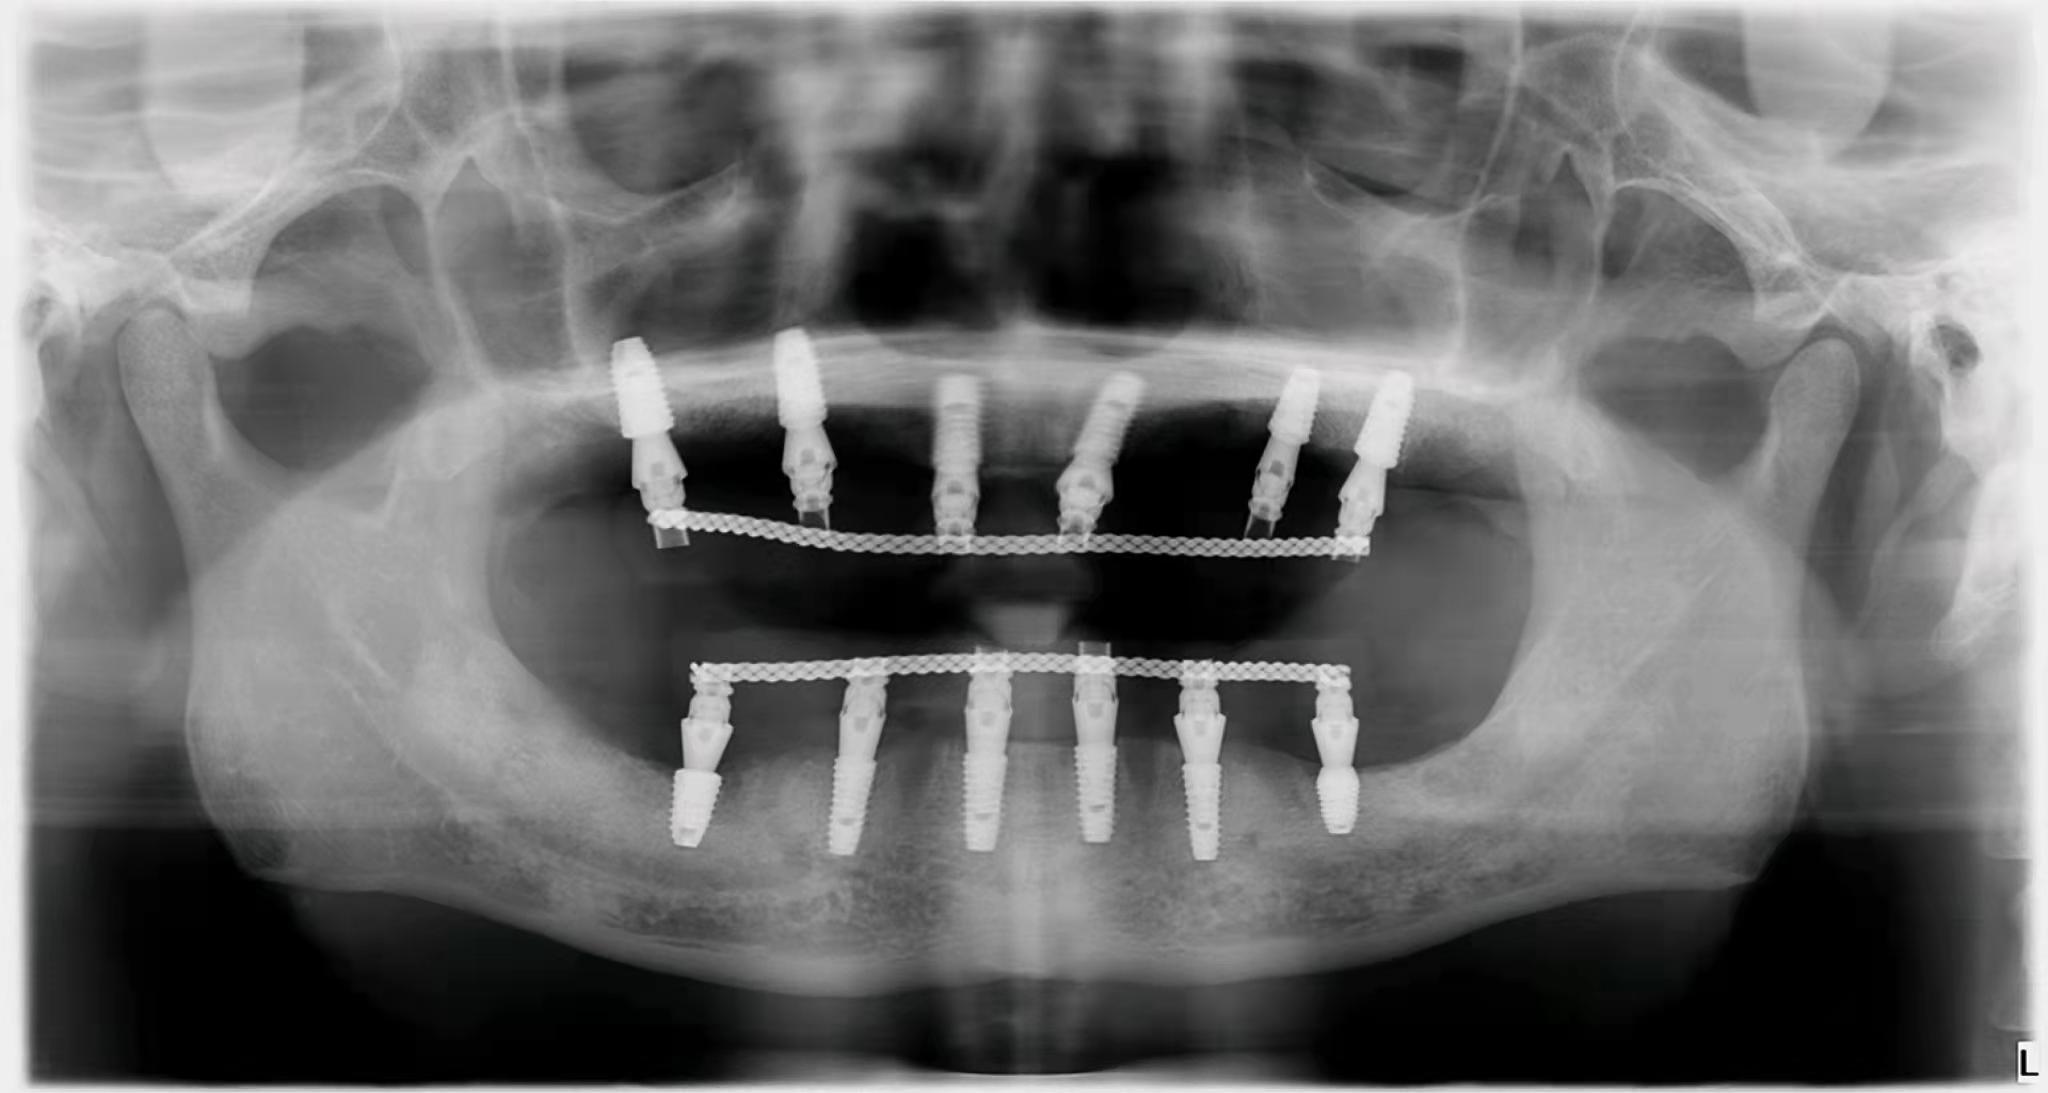

3. 種植牙價(jià)格降低在公立和私立口腔中,與種植體不同的是,國(guó)內(nèi)部分牙冠品牌已經(jīng)被大眾接受。如果是單顆牙缺失,預(yù)算有限,可以找醫(yī)生咨詢低成本方案。即使是全口或者半口牙缺失,需要種植,也不需要在牙窩上全部種植,可以用all-one-4,或者all-one-6。